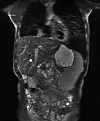

MR-scanning af Silas i marts 2019. Til venstre ses den metalstent, der blev indsat i Silas’ fjerde og nuværende lever. Stenten presser galdegangen åben indefra, så galden kan flyde normalt til tarmen.